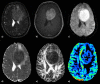

The role of conventional Magnetic Resonance Imaging (MRI) in the detection of cerebral tumors has been well established. However its excellent soft tissue visualization and variety of imaging sequences are in many cases non-specific for the assessment of brain tumor grading. Hence, advanced MRI techniques, like Diffusion-Weighted Imaging (DWI), Diffusion Tensor Imaging (DTI) and Dynamic-Susceptibility Contrast Imaging (DSCI), which are based on different contrast principles, have been used in the clinical routine to improve diagnostic accuracy. The variety of quantitative information derived from these techniques provides significant structural and functional information in a cellular level, highlighting aspects of the underlying brain pathophysiology. The present work, reviews physical principles and recent results obtained using DWI/DTI and DSCI, in tumor characterization and grading of the most common cerebral neoplasms, and discusses how the available MR quantitative data can be utilized through advanced methods of analysis, in order to optimize clinical decision making.